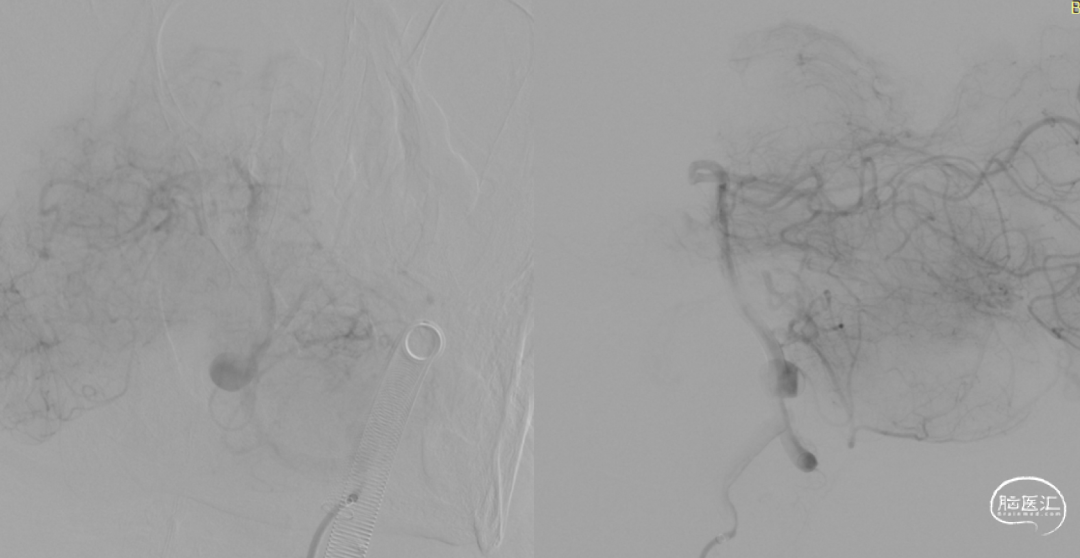

术前造影:

左颈。

J-Tube™打开过程-整体显影性能良好。

J-Tube™血流导向密网支架打开过程。

释放J-Tube™血流导向密网支架。

释放支架后造影,可见血液滞留明显。